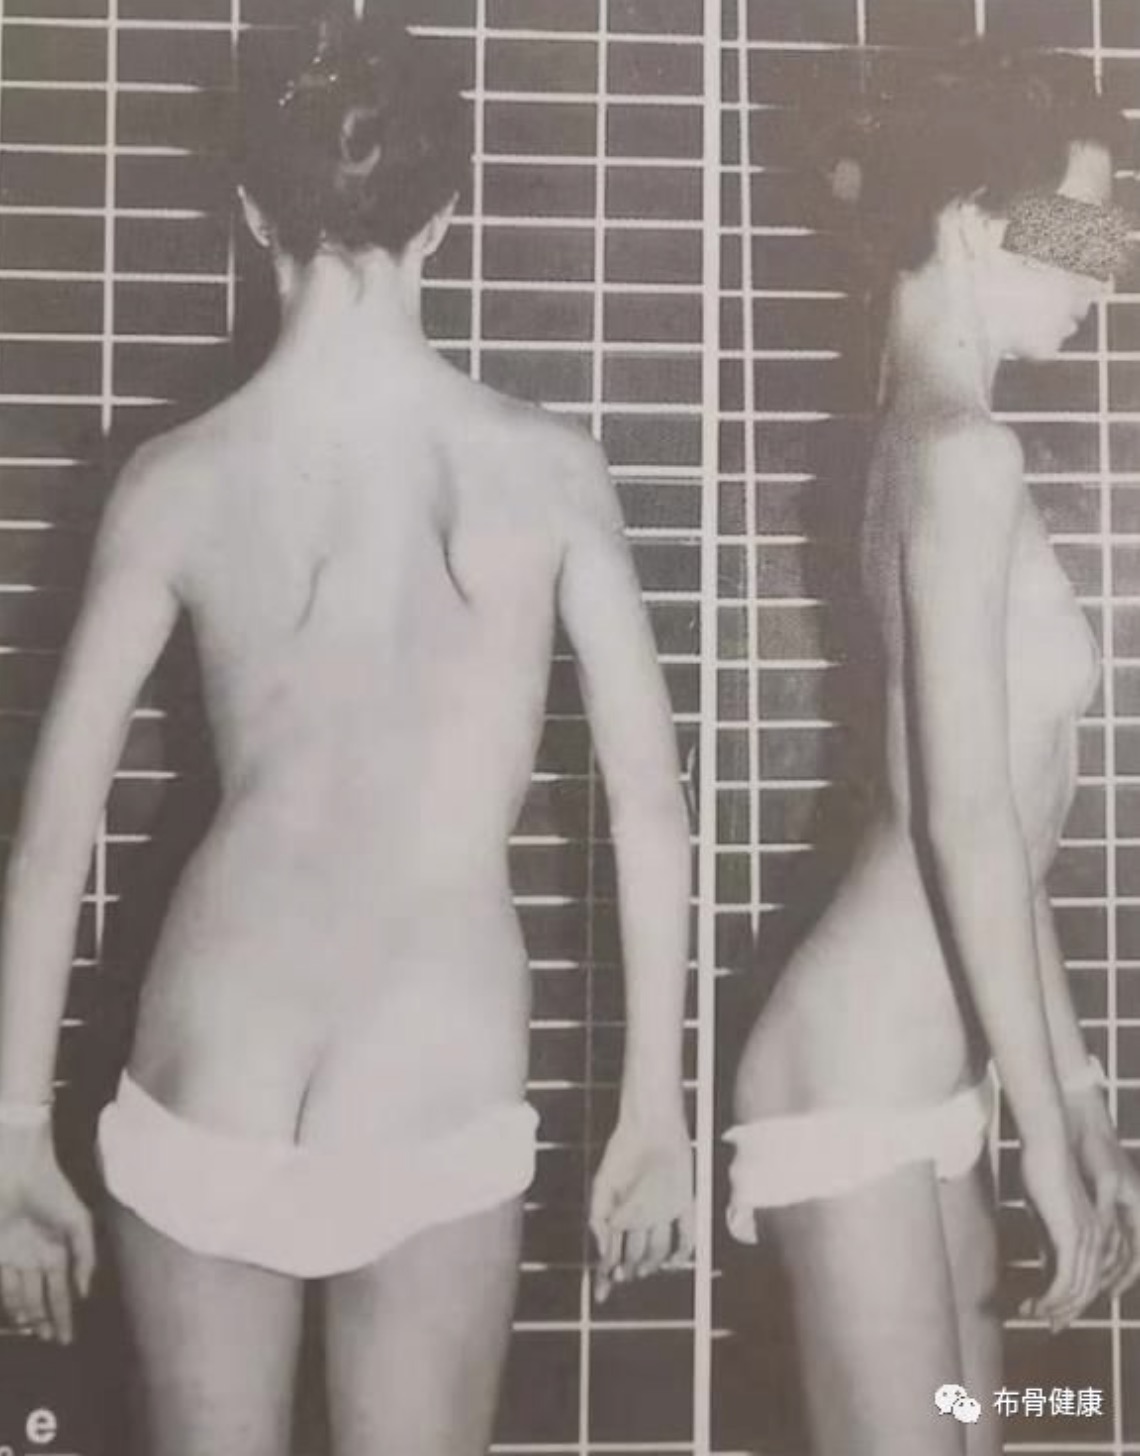

- 脊椎侧弯对健康的影响,除了体态外观上的问题外,多半会引起长期的腰背酸痛,另外脊椎关节在长期受力不均之下,可能发生退行性关节炎;如果侧弯持续增大,可影响心肺功能;非常严重的畸形也可能会压迫神经根和脊髓,引起瘫痪。对于脊柱侧弯,早期发现非常重要,家长有助于早期发现,那么,如何能早期发现孩子患有脊柱侧弯呢.....

- 脊柱侧弯学名脊柱侧凸,孩子患了脊柱侧凸,家长都比较着急,四处寻医,奔波折腾,心里没有底,小编组织了有关脊柱侧弯的一些问题,希望患者和家长正确认识,回归理性! 本期主要内容:认识脊柱侧凸,脊柱侧凸的病因、筛查常见的问题。 下期内容:脊柱侧凸研究进展、治疗方案、支具方面的问题。 文章来源: 国际.....